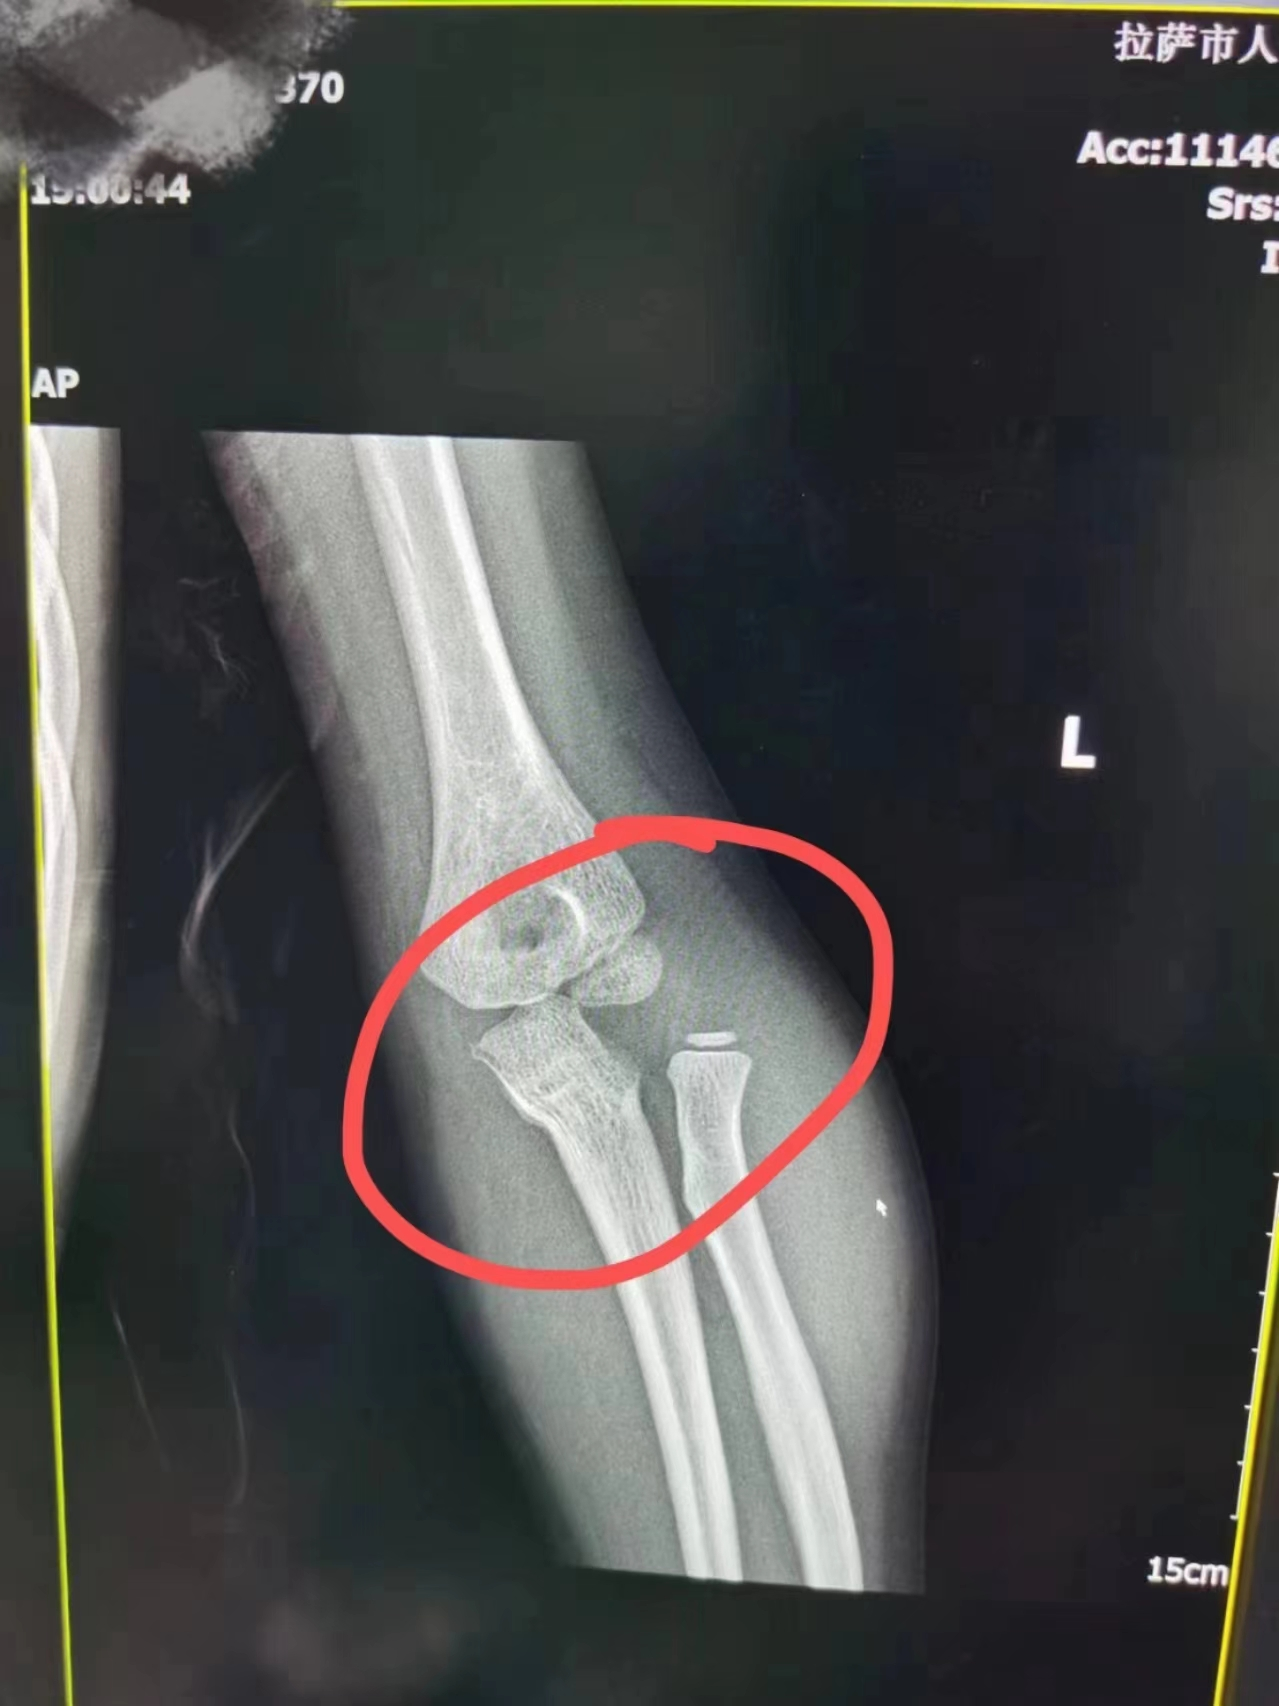

抵达医院时,然然的肘关节已高度肿胀,影像学检查显示左侧尺骨近端成角畸形,桡骨头向外侧脱位,情况十分复杂。“我们在深入讨论后,决定再次尝试手法复位,利用前后夹石膏进行了固定,完成后检查显示,骨折复位良好,肱桡关系对位对线佳。三天后,MR复查结果同样令人满意,确认了复位的成功。”该院骨科副主任医师陈文建说道。